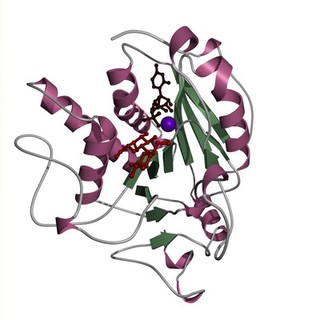

Alpha 1,3 galactosyl transferase

K R Acharya